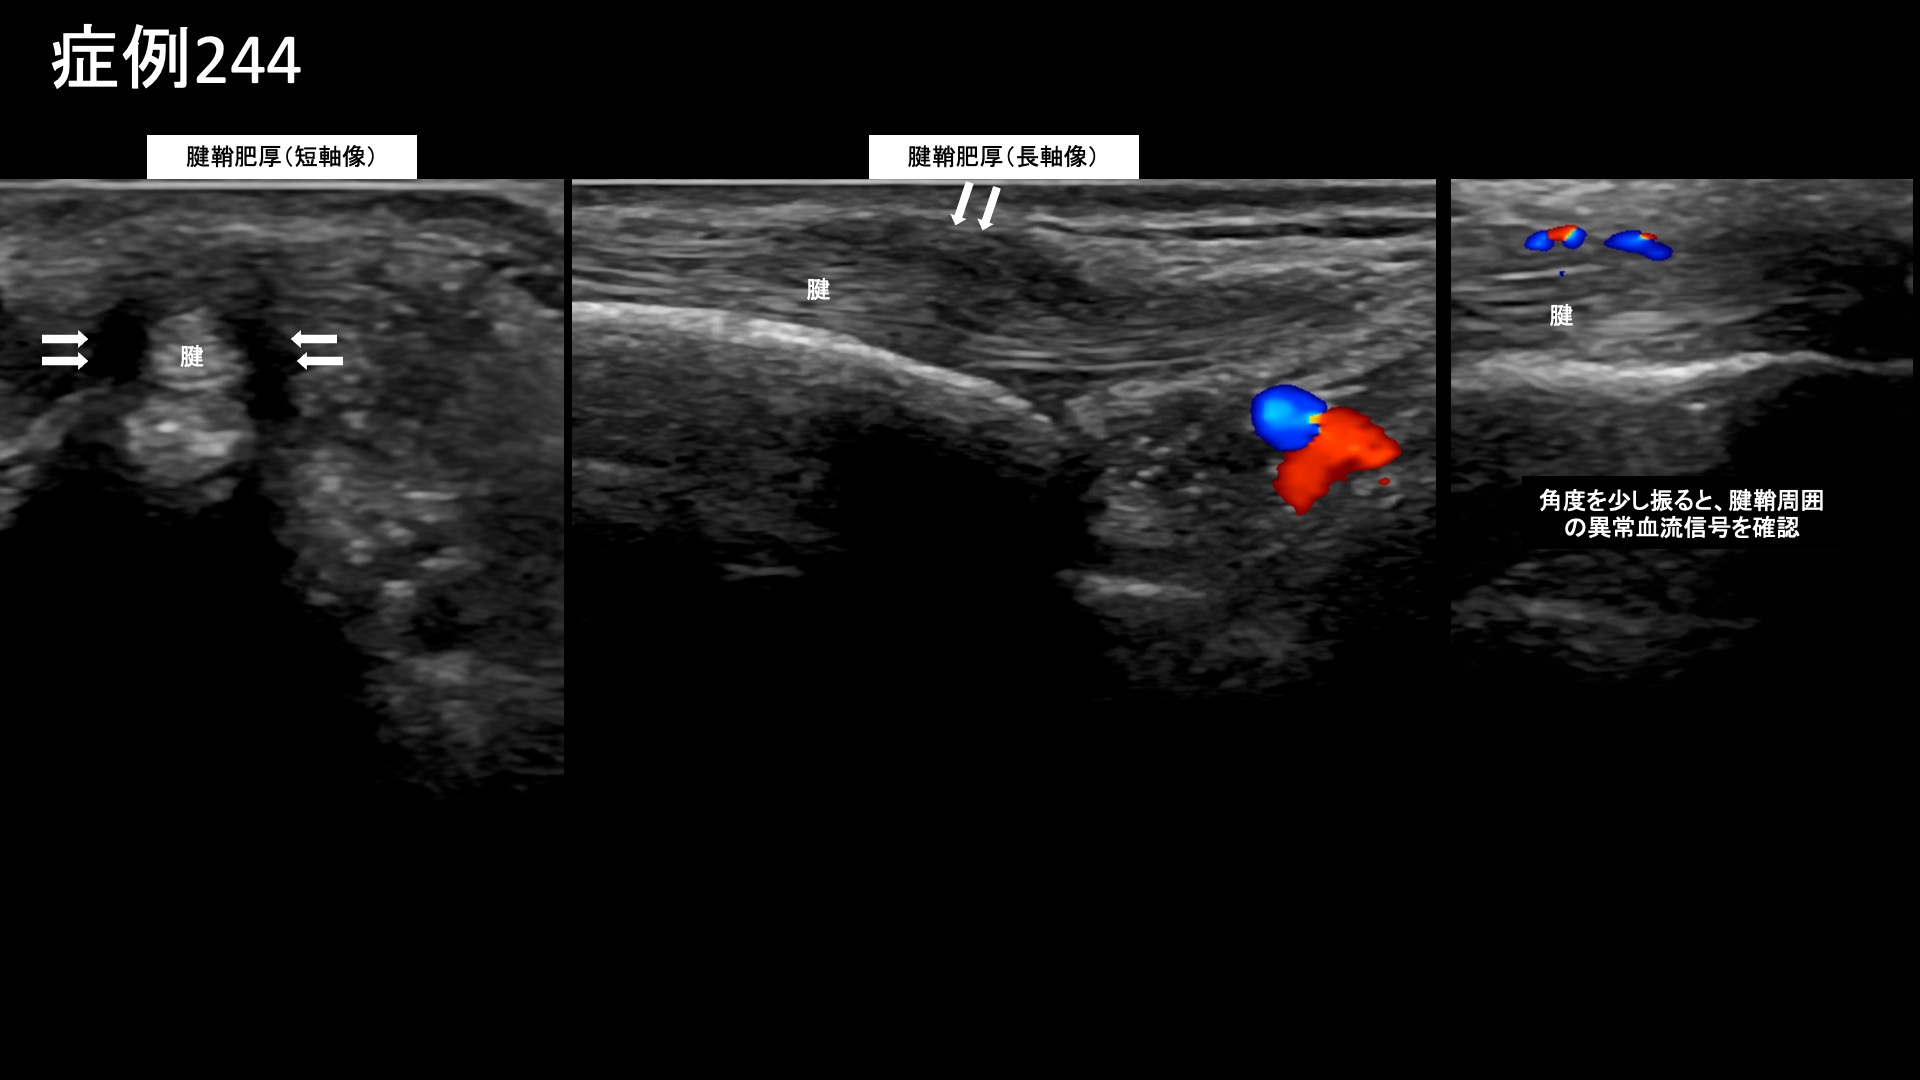

手:ばね指など 【40代:女性】繰り返すステロイド注射でもよくならなかったドゥケルバン腱鞘炎に対するモヤモヤ血管治療(ドゥケルバン腱鞘炎、ドケルバン腱鞘炎、手首親指側の痛み) 2025.10.20 鴨井院長による動画解説 受診までの経過 9ヶ月前に床に手を着いた際に、右手首を痛めてしまいました。整形外科で診てもらうと、腱鞘炎のほか、CM関節症も指摘されました。ステロイド注射を受けると一旦は改善するのですが、1ヶ月ほどで元に戻ってしまうため、それ以降は注射を止めました。しかしながら、症状は増悪し、痛みは前腕まで広がりました。安静にしていても痛みが出るようになり、冷えるとさらに痛みが増しました。ステロイド注射以外の治療方法を求めて当院を受診されました。 診察時の所見 尺屈で痛みが誘発され、手首の親指側の腱をエコーで観察すると、腱鞘の腫脹および周囲の(モヤモヤ血管を反映した)異常血流信号を認めました。腱は保たれていました。典型的なドゥケルバン腱鞘炎の所見です。一方、CM関節の変形はそれほど目立たず、同部位についても腱鞘炎が主体と考えられました。治療適応と判断し、モヤモヤ血管(病的新生血管)に対する運動器カテーテル治療(微細動脈塞栓術)を受けていただきました。 治療の所見 血管造影を行うと、橈骨動脈造影で前述の腱鞘肥厚部と、CM関節周囲に一致してモヤモヤ血管が濃染像として描出されました。治療後は画像上速やかに消失しました。その他前腕を含む複数箇所の治療を行い終了しました。 治療前画像:損傷を受ける、あるいは繰り返しのストレスにより発生した異常な新生血管 治療後画像:カテーテルを用いて塞栓物質を血管内に投与し新生血管を塞いだ状態 治療費用:治療する部位によって費用が異なりますのでこちらをご参照ください。 主なリスク・副作用等:針を刺した場所が出血により腫れや痛みを生じたり、感染したりすることがあります(穿刺部合併症)。造影剤によるアレルギー(皮膚のかゆみ・赤み・息苦しくなるなどの症状)が出ることがあります。 治療後の経過 治療後2週間で右手首橈側の痛みは半減しました。他の部位の痛みはほぼ消失しました。ハサミも使えるようになりました。その後も再燃することなく順調に経過され、治療後3ヶ月では9割方の痛みは改善しました(1/10程度)。仕事で手首を酷使するため、その際には多少痛むことがあるものの休めば治ります。エコー検査では腱鞘肥厚は残っているものの、炎症所見は消失していました。残存症状についても自然経過で解消されることが見込まれたため終診としました。安静時にも生じるほどの痛みであり、前腕にもその痛みが広がるなど、重症度の高い腱鞘炎でした。モヤモヤ血管治療によりほぼ完治しましたが、画像では腱鞘肥厚などは残る場合が多いです。これは痛みが消失した場合でも同様です。やはり、人間の腱や腱鞘、靭帯というのは消耗品であり、加齢により少しずつ変性し、傷んでいきます。残ったものを大切に使うという考え方も重要です。これまでよく頑張ってきた手首に感謝しながら、大切に使っていっていただきたいと思います。尚、ステロイド注射を繰り返すと組織を傷める懸念があります。使用する場合は、その量や頻度、そして何より使用目的を厳密に管理、判断する必要があります。 ドケルバン病の詳細はこちら 【50代:男性】ヘルニアによる腰部神経根症が原因の腰臀部痛に対して、減量とカテーテル治療を行い完治した症例(腰椎椎間板ヘルニア、椎間孔狭窄、神経根症、減量/マンジャロ) 前の記事 【70代:女性】発症10ヶ月の額から眉にかけての帯状疱疹後神経痛に対するカテーテル治療(帯状疱疹後神経痛、頭部顔面の痛み) 次の記事